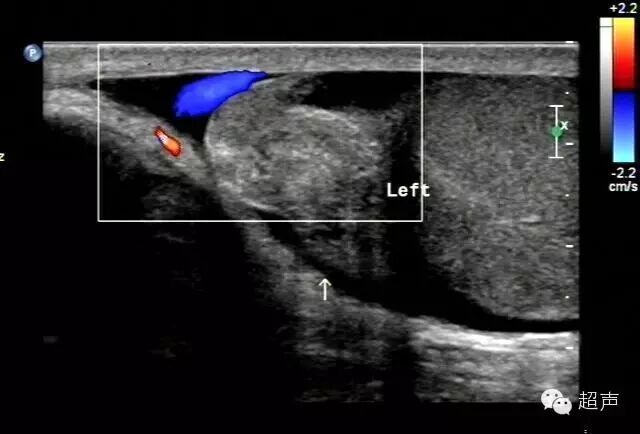

③超过24 h二维声像主要表现患侧睾丸增大,回声强弱不均,可见弥漫性高回声。可见裂隙状的低回声,边缘向内凹陷呈蚕豆状。大于10 d的,肿大的睾丸开始缩小,可小于对侧,回声减低,呈低回声,不均匀,可伴有钙化点。 少数病例睾丸周围开始出现一低回声“晕”,彩色多普勒显示为“彩色晕环”。

75%为左侧扭转。

早期二维图像难以鉴别,主要依靠彩色多普勒进行鉴别。 CDFI显示睾丸扭转时血流减少或消失,而炎症时血流增多。值得注意的是当睾丸扭转松解时,可发生局部充血性改变,这是缺血组织血流重新灌注的“反跳反应” 。